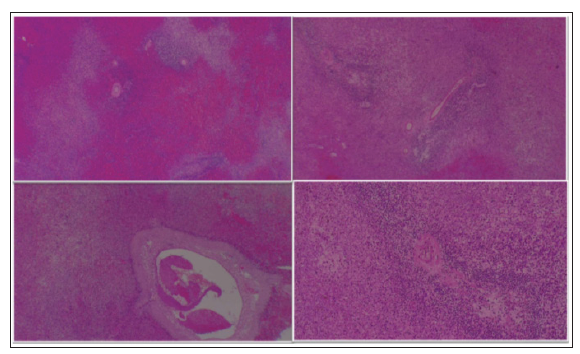

Puesto que presentaba sangrado persistente y anemia severa, se inició manejo con terapia trans-fusional, siendo necesaria la transfusión de una unidad de glóbulos rojos y de 1 aféresis de plaquetas cada 12 horas, junto con un pulso de 40 mg de Dexametasona cada 24 horas por 4 dias, dando continuidad a la misma dosis de Eltrombopag®; sin embargo, con persistencia de recuentos plaquetarios bajos sintomáticos. Considerando el riesgo de sangrado perioperatorio, fue llevada inicialmente a embolización de arteria esplénica con microesferas por cirugia vascular al cuarto dia de hospitalización sin mejoría. Presentó ruptura esplénica secundaria a la embolización, por lo que el sexto dia de estancia hospitalaria fue llevada a esplenectomia abierta (figura 1).

Figuras 1 a-d; 1 a y b: tejido esplénico con congestión y hemorragia con evidencia de trombosis venosa; 1 c: tejido esplénico con zonas de necrosis isquémica en el 30 % de la muestra; 1 d: imagen con folículos linfoides secundarios normales.